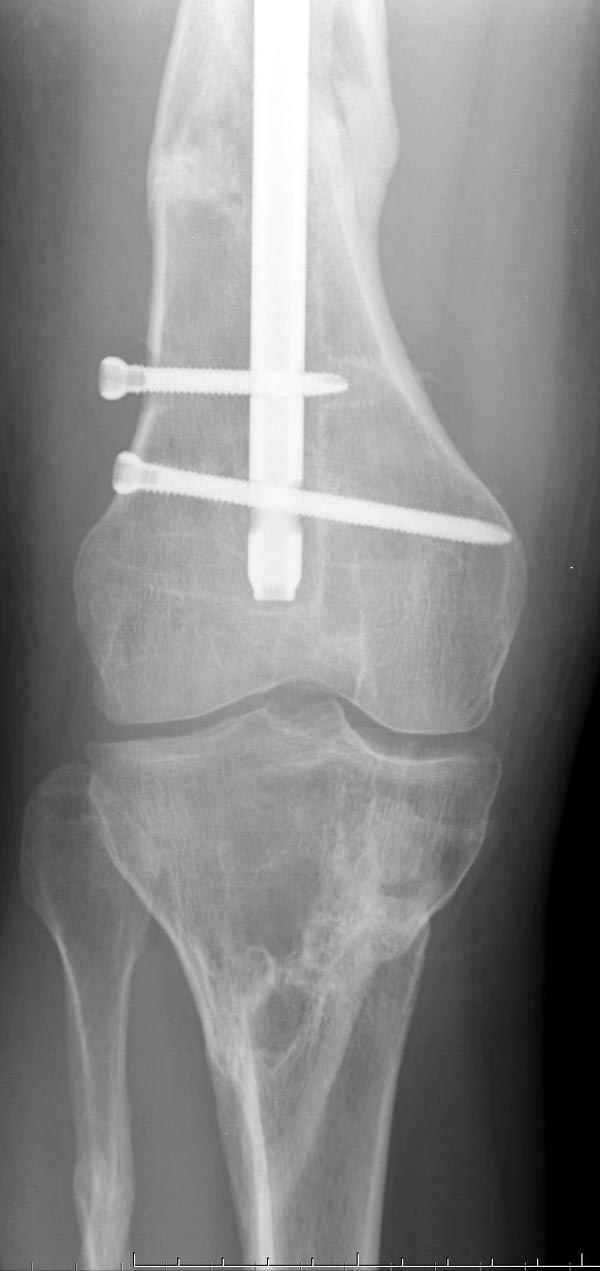

Рутинный интрамедуллярный остеосинтез с расверливанием и с фиксацией реконструктивным трокантерик штифтом (рис №1, №2),

если первые 4 месяца послеоперационного периода проходил без проблем, но на 5 месяце появились боли в дистальном отделе бедра и температура, т.е. симптомы медуллярного инфицирования (рис №3, №4).

Замена реконструктивного штифта “Custom made Nail” с антибиотиком (рис №5, №6),

после промывки канала с рассверливанием внутреннего кортекса, через 4 недели антибиотический штифт удалили, оспалителный процесс остановлен и бедро сросся.